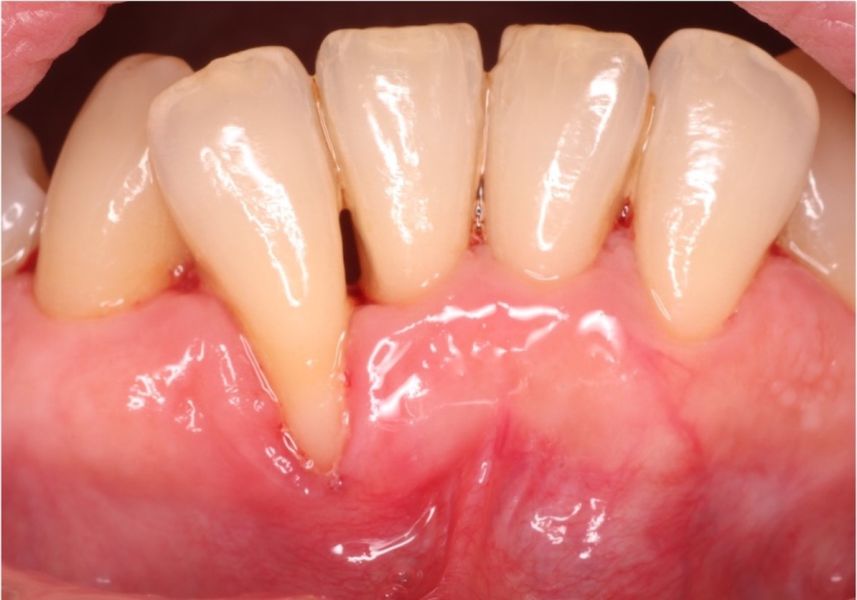

Foto inicial con gran cantidad de placa y sarro acumulado.

La recesión gingival o de encías es una retracción de la encía que deja al descubierto la raíz del diente que anteriormente estaba cubierta por la encía.

La recesión gingival puede producir sensibilidad dental, inflamación gingival, sangrado o dificultad de cepillado. Igualmente, crea problemas estéticos, ya que el diente se ve más largo. Existen casos donde la recesión progresa de forma descontrolada y puede causar la pérdida del diente.